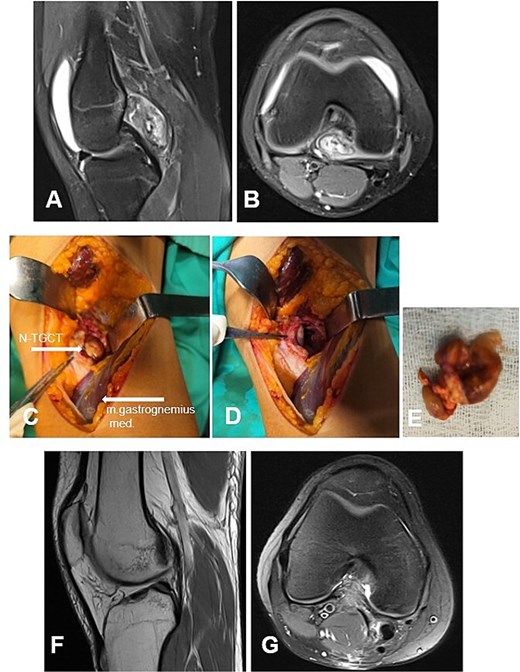

Case 5. (A and B) Preoperative sag and ax MRI TSE PD FS—lobulated edematosus intra-articular neoplasm with a posterior mediocentral localization. (C and D) Posterior synovectomy between m. semitendinosus and m. gastrognemius medialis. (Е) Macroscopic appearance of the N-TGCT measuring 3 × 2 × 2 cm after excision. (F and G) Postoperative 12 m. Sag and Ax MRI TSE PD FS—no evidence of recurrence of the resected neoplasm. PD FS, proton density weighting with fat suppression; TSE, turbo spin echo.

А 16-year-old female athlete presented with knee effusion and pain without preceding trauma, persisting for 3 months. Diagnostic MRI revealed an intra-articular, retrocondylar mass with intact cruciate ligaments and menisci (Fig. 6A and B). The lesion was identified as a nodular tenosynovial giant cell tumor and was excised through a posterior partial synovectomy using a medial approach with lateral retraction of the m. gastrocnemius medialis. The tumor was removed sharply and en bloc within macroscopically healthy synovial margins (Fig. 6C–E). At the 12-month postoperative follow-up, the patient was asymptomatic, with no MRI evidence of local recurrence (Fig. 6F and G). Successful return to full athletic activity.